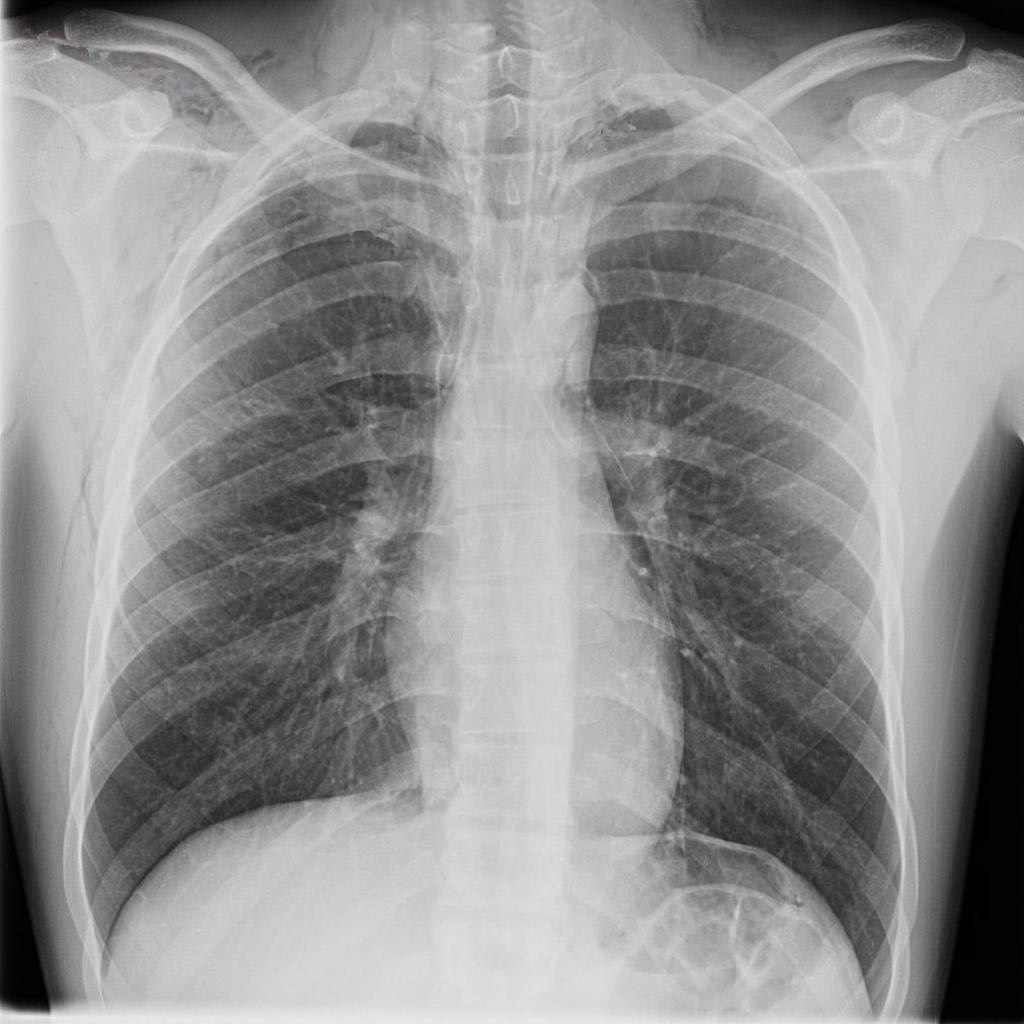

2849. Учитывая представленные на рентгенограмме органов грудной клетки данные,

основным объективным признаком спонтанного пневмомедиастинума в данном случае является

2849. Учитывая представленные на рентгенограмме органов грудной клетки данные, основным объективным признаком спонтанного пневмомедиастинума в данном случае является